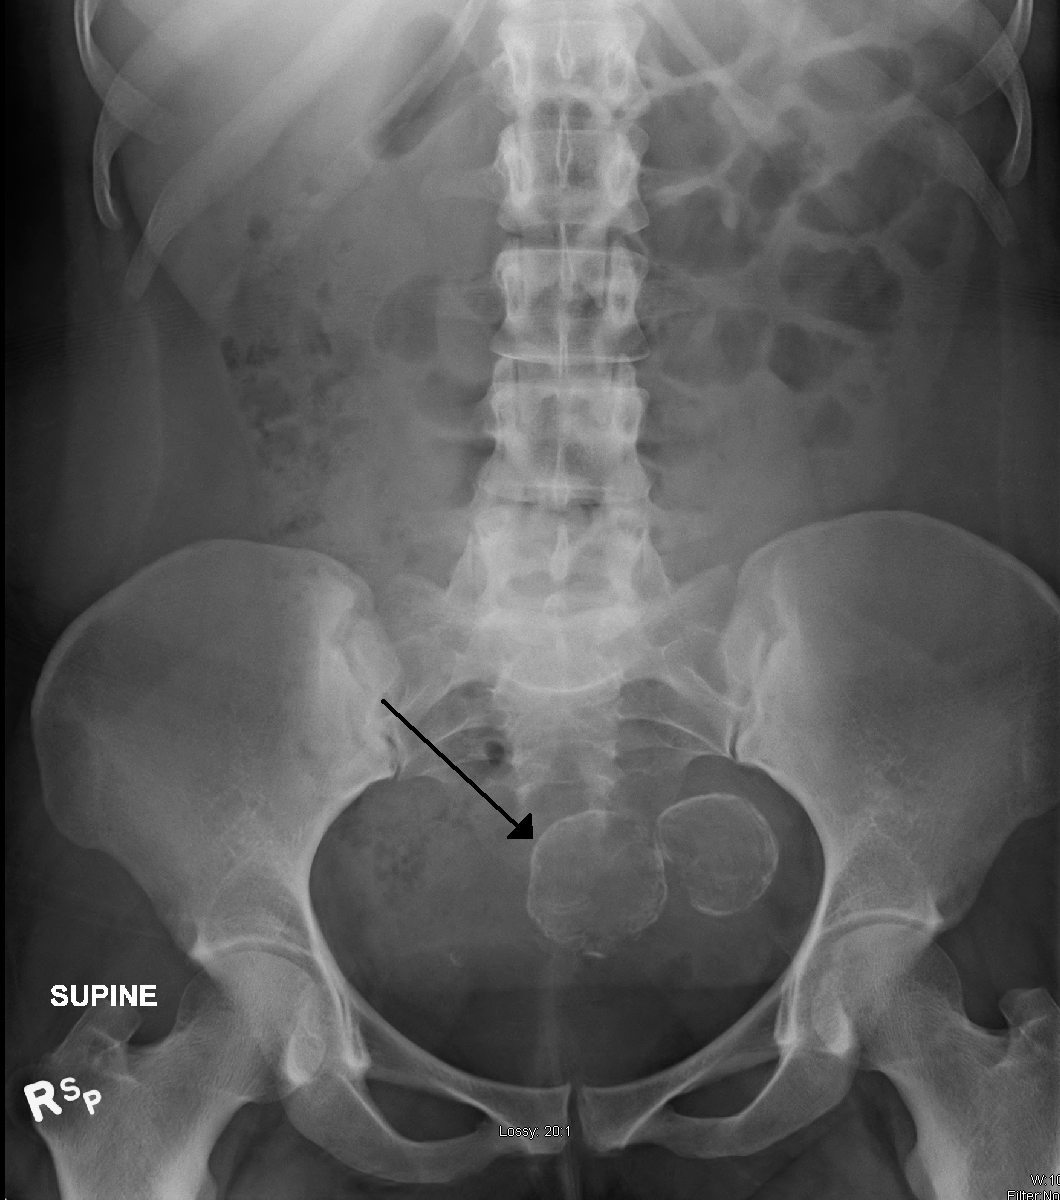

초음파 검사, MRI, 자궁경을 통해 자궁근종을 진단한다. 특히 MRI는 많은 정보를 제공한다. 자궁근종은 T1 강조 영상(T1WI)에서 저신호 또는 등신호, T2 강조 영상(T2WI)에서 저신호를 보이는 것이 일반적이다. 그러나 자궁근종 내 혈액 순환 장애로 인해 충혈, 유리화, 낭포화, 석회화, 지방 변성, 괴사 등 다양한 이차적 변화가 발생하여 다양한 신호 강도를 보일 수 있다. 종양 직경이 8cm를 초과하면 악성 종양일 가능성을 고려해야 한다.

골반 검사와 초음파 검사만으로도 대부분의 환자에게서 자궁근종을 진단하기에 충분하다. 초음파 검사 결과가 불분명할 경우, 자기 공명 영상(MRI)을 통해 대부분 자궁근종 진단을 확진할 수 있다. 또한 MRI는 비정형 영상 특징을 보이는 양성 자궁근종과 변이 성장 패턴을 보이는 자궁근종을 식별할 수 있다. MRI는 자궁근종과 유사하게 보이거나 환자의 증상에 기여할 수 있는 다른 자궁 질환(예: 자궁선근증, 자궁내막 용종, 자궁내막암) 및 자궁 외 질환(예: 양성 및 악성 난소 종양, 자궁내막증)도 식별할 수 있다.[33] 그러나 자궁근종의 작은 비율은 사용 가능한 모든 영상 검사(예: 초음파, CT, MRI 및 PET-CT)에서 다른 악성 자궁 종양(예: 평활근육종)과 유사하게 보일 수 있다.[33]자궁벽의 악성 종양(예: 평활근육종)은 매우 드물다. 양성 근종보다 악성 자궁 종양을 시사하는 소견으로는 빠르거나 예상치 못한 성장(특히 폐경기 이후), 자궁내막 줄무늬의 중단/소실, 림프절 비대, 인접 장기 침범 및 원격 장기(예: 폐) 전이 등이 있다. 악성을 시사하는 MRI 소견으로는 결절성/불분명한 종양 경계, 고형 종양 성분의 중간/높은 T2 강조 신호 강도, 아급성 출혈과 일치하는 높은 신호 T1 강조 시퀀스 영역, 종양의 고형 부분의 미세한/흐릿한 조영 증강, 확산 강조 영상(DWI)에서 확산 제한 등이 있다.[33] 생검은 드물게 수행되며, 수행하더라도 진단적이지 않은 경우가 많다. 초음파 및 MRI 영상 검사 후 진단이 불확실한 경우 일반적으로 수술이 권장된다.[34]

골반 검사와 초음파 검사만으로도 대부분의 환자에게서 자궁근종을 진단하기에 충분하다. 초음파 검사 결과가 불분명할 경우, 자기 공명 영상(MRI)을 통해 대부분 자궁근종 진단을 확진할 수 있다.[33] 초음파 검사, 자기 공명 영상(MRI), 자궁경을 통해 관찰한다.4. 3. 자기공명영상(MRI)

골반 검사와 초음파 검사만으로도 대부분 자궁근종 진단이 가능하지만, 초음파 검사 결과가 불분명한 경우 자기공명영상(MRI)을 통해 확진할 수 있다.[33] MRI는 비정형적인 양성 자궁근종과 변이 성장 패턴을 보이는 자궁근종을 식별할 수 있다.[33] 또한, 자궁근종과 유사하게 보이거나 증상에 영향을 줄 수 있는 다른 자궁 및 자궁 외 질환(예: 자궁선근증, 자궁내막 용종, 자궁내막암, 양성 및 악성 난소 종양, 자궁내막증)을 식별하는 데에도 도움이 된다.[33]하지만 일부 자궁근종은 사용 가능한 모든 영상 검사(예: 초음파, CT, MRI, PET-CT)에서 다른 악성 자궁 종양(예: 평활근육종)과 유사하게 보일 수 있다.[33] 악성 종양을 시사하는 소견으로는 빠르거나 예상치 못한 성장(특히 폐경기 이후), 자궁내막 줄무늬 중단/소실, 림프절 비대, 인접 장기 침범, 원격 장기(예: 폐) 전이 등이 있다. 악성을 시사하는 MRI 소견으로는 결절성/불분명한 종양 경계, 고형 종양 성분의 중간/높은 T2 강조 신호 강도, 아급성 출혈과 일치하는 높은 신호 T1 강조 시퀀스 영역, 종양 고형 부분의 미세/흐릿한 조영 증강, 확산 강조 영상(DWI)에서 확산 제한 등이 있다.[33]

초음파 검사, MRI, 자궁경을 통해 관찰하며, 특히 MRI를 통한 진단으로 얻을 수 있는 정보가 많다. 자궁근종은 기본적으로 T1WI에서 저~등 신호, T2WI에서 저 신호를 나타낸다. 자궁근종 내에는 혈행 장애가 있기 때문에 근종은 충혈되기 쉽고, 유리화, 낭포화, 석회화, 지방 변성, 괴사 등의 이차성 변화를 일으키므로 다양한 신호가 나타나는 것으로 알려져 있다.